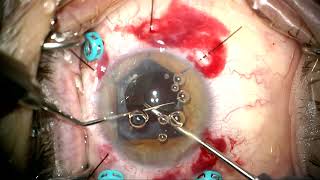

Complex optic capture of dislocated lens and PPV by Steven G. Safran MD video

Complex optic capture of dislocated lens and PPV by Steven G. Safran MD

Complex optic capture of dislocated lens and PPV by Steven G. Safran MD Dislocated IOL exchange/optic capture/PPV/floaterectomy by Steven G. Safran MD

Complex optic capture of dislocated lens and PPV by Steven G. Safran MD

Complex optic capture of dislocated lens and PPV by Steven G. Safran MD Dislocated IOL exchange/optic capture/PPV/floaterectomy by Steven G. Safran MD